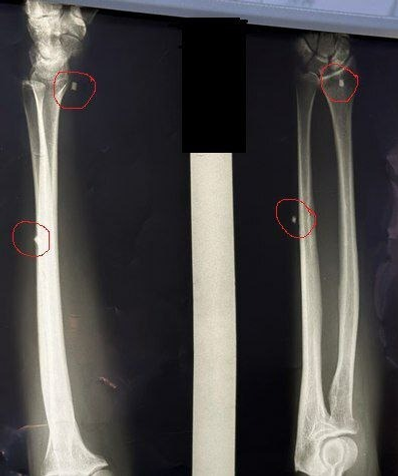

В городской больнице Салавата успешно прошла уникальная операция для участника специальной военной операции из Кугарчинского района. Об этом сообщает ИА «Башинформ» со ссылкой на Министерство здравоохранения Республики.

Операцию провёл нейрохирург Арслан Асылбаев. В настоящее время военнослужащий проходит курс реабилитации, и подвижность его руки постепенно восстанавливается.

Фото:Городская больница города Салават